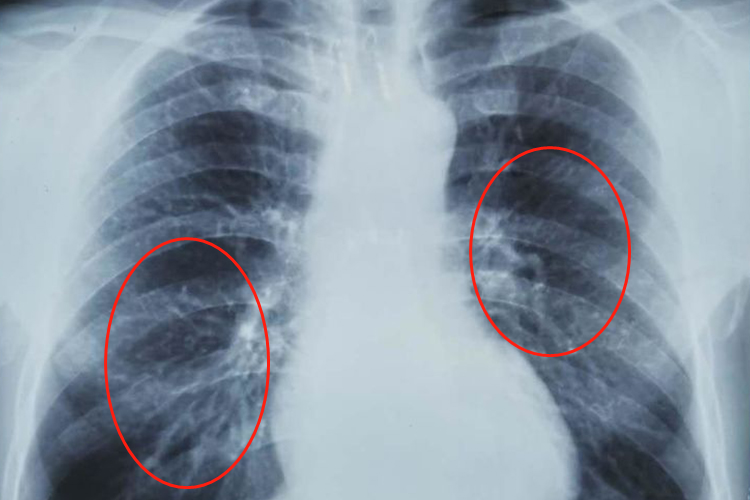

尘肺是肺尘埃沉着病的简称,是指在职业活动中长期吸入生产性矿物性粉尘,并在肺内潴留而引起的以肺组织弥漫性纤维化为主的疾病。尘肺一期的高千伏胸片常表现为有总体密集度1级的小阴影,分布范围为1-2个肺区,可同时出现胸膜斑。

确诊尘肺病后,应立即脱离粉尘作业,此外还应戒烟,避免生活性粉尘,定期体检等。建议患者尽快就诊,可在医生指导下应用沙丁胺醇气雾剂、氨茶碱缓释片等平喘治疗,舍雷肽酶肠溶片等祛痰治疗。